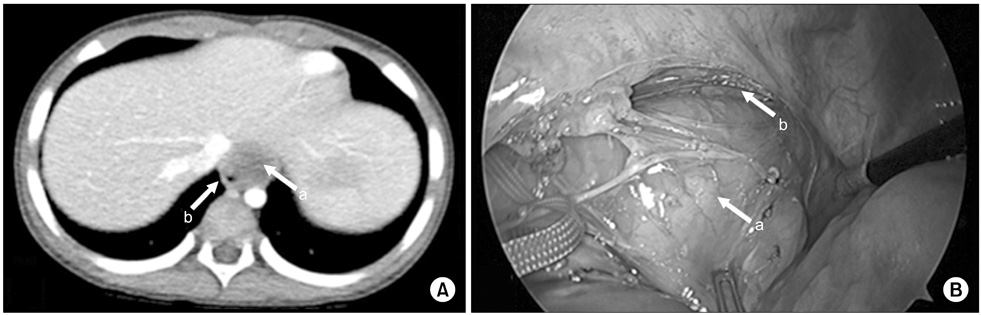

Venous malformation. (A) There was mass at cardoiphrenic angle and it was suspected an inflammatory pseudo-tumor or congenital lung lesion like cystic lymphangioma on chest CT (3.0×3.6×2.3-cm-sized mass). (B) It was being originated from right pleura and was resected clearly. Arrows: a, mass; b, lung; c, diaphragm.

Fig. 7 Venous malformation. (A) There was mass at cardoiphrenic angle and it was suspected an inflammatory pseudo-tumor or congenital lung lesion like cystic lymphangioma on chest CT (3.0×3.6×2.3-cm-sized mass). (B) It was being originated from right pleura and was resected clearly. Arrows: a, mass; b, lung; c, diaphragm.